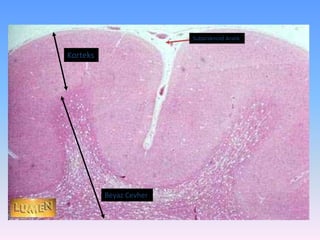

 Histolojik kesitlerde beyin (serebrum), beyincik (serebellum)

ve omurilikte (medulla spinalis), beyaz (ak madde) ve gri (boz

madde) renkli bölgeler görülür. Bu durum miyelinin farklı

dağılımından ileri gelir.

 Beyin ve beyinciğin korteksini gri madde oluştururken,

merkezini ak madde doldurur.